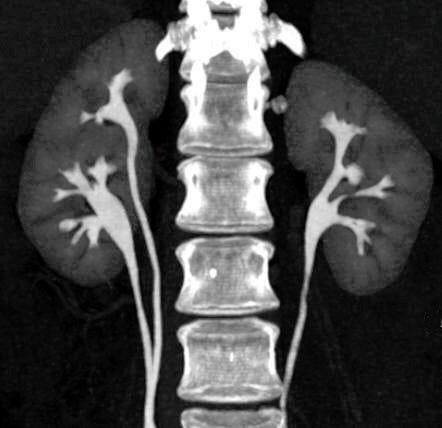

In a January 2023 preprint in The Lancet, the New Zealand government released a study showing a 70 percent increased rate of kidney injury following two doses of Pfizer mRNA vaccines. Even more telling of injury was the dose-dependent effect. That is, one dose of Pfizer showed a 60 percent increased rate of injury within three weeks post-injection, while two doses showed a 70 percent increased rate of injury three weeks post-injection. “Acute kidney injury” was not defined by the authors but is understood in a clinical setting to include measurable changes in lab results and/or serious signs and symptoms such as bleeding, pain with urination, kidney stones, nephritis, nephrotic syndrome, or other renal dysfunction.

That study did not discuss the time elapsed from vaccination to glomerulonephritis pathology. This smaller study of 13 patients found that the median time of onset was one week after the first dose and four weeks after the second dose. [7] The patients typically presented with acute kidney injury, edema, and visible blood in the urine.

Minimal change disease is not one of the conditions noted in the Pfizer adverse events list. It is an insidious kidney disorder that is so named for the very subtle changes in the glomeruli filtration, which leaves gaps in filtration. Nephrotic syndrome results, in which proteins leak through the gaps from the blood into the urine, and then systemic effects of hypoproteinemia result.